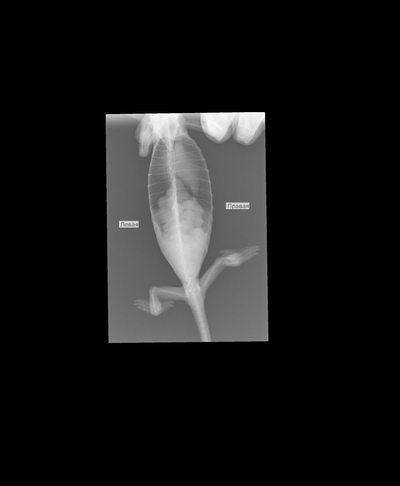

Было назначено: сдача стула на паразитов, рентген плюс анализ крови, чтобы хоть как-то попытаться определить причину болезни.

Проблем с паразитами не было, а вот на рентгене был какой то не переваренный кусок еды. Это могло быть что-то из декора, что он по глупости съел и теперь не может из себя вывести. Тогда пришлось бы делать операцию.